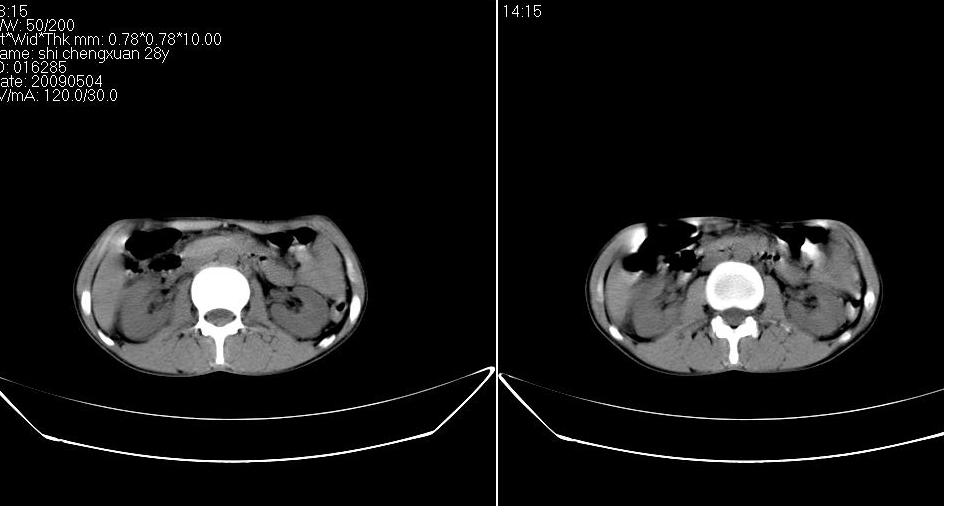

标题: CT19774:上腹部CT平扫

女 28岁,急诊,腹疼一天。

胰体尾部较胖,是不是有胰腺炎?

胆囊底部囊壁增厚,考虑胆囊炎。胰腺改变考虑为部分容积效应。

不排除胰腺炎可能;建议查血尿淀粉酶。

图像不是很清楚,胰腺炎?